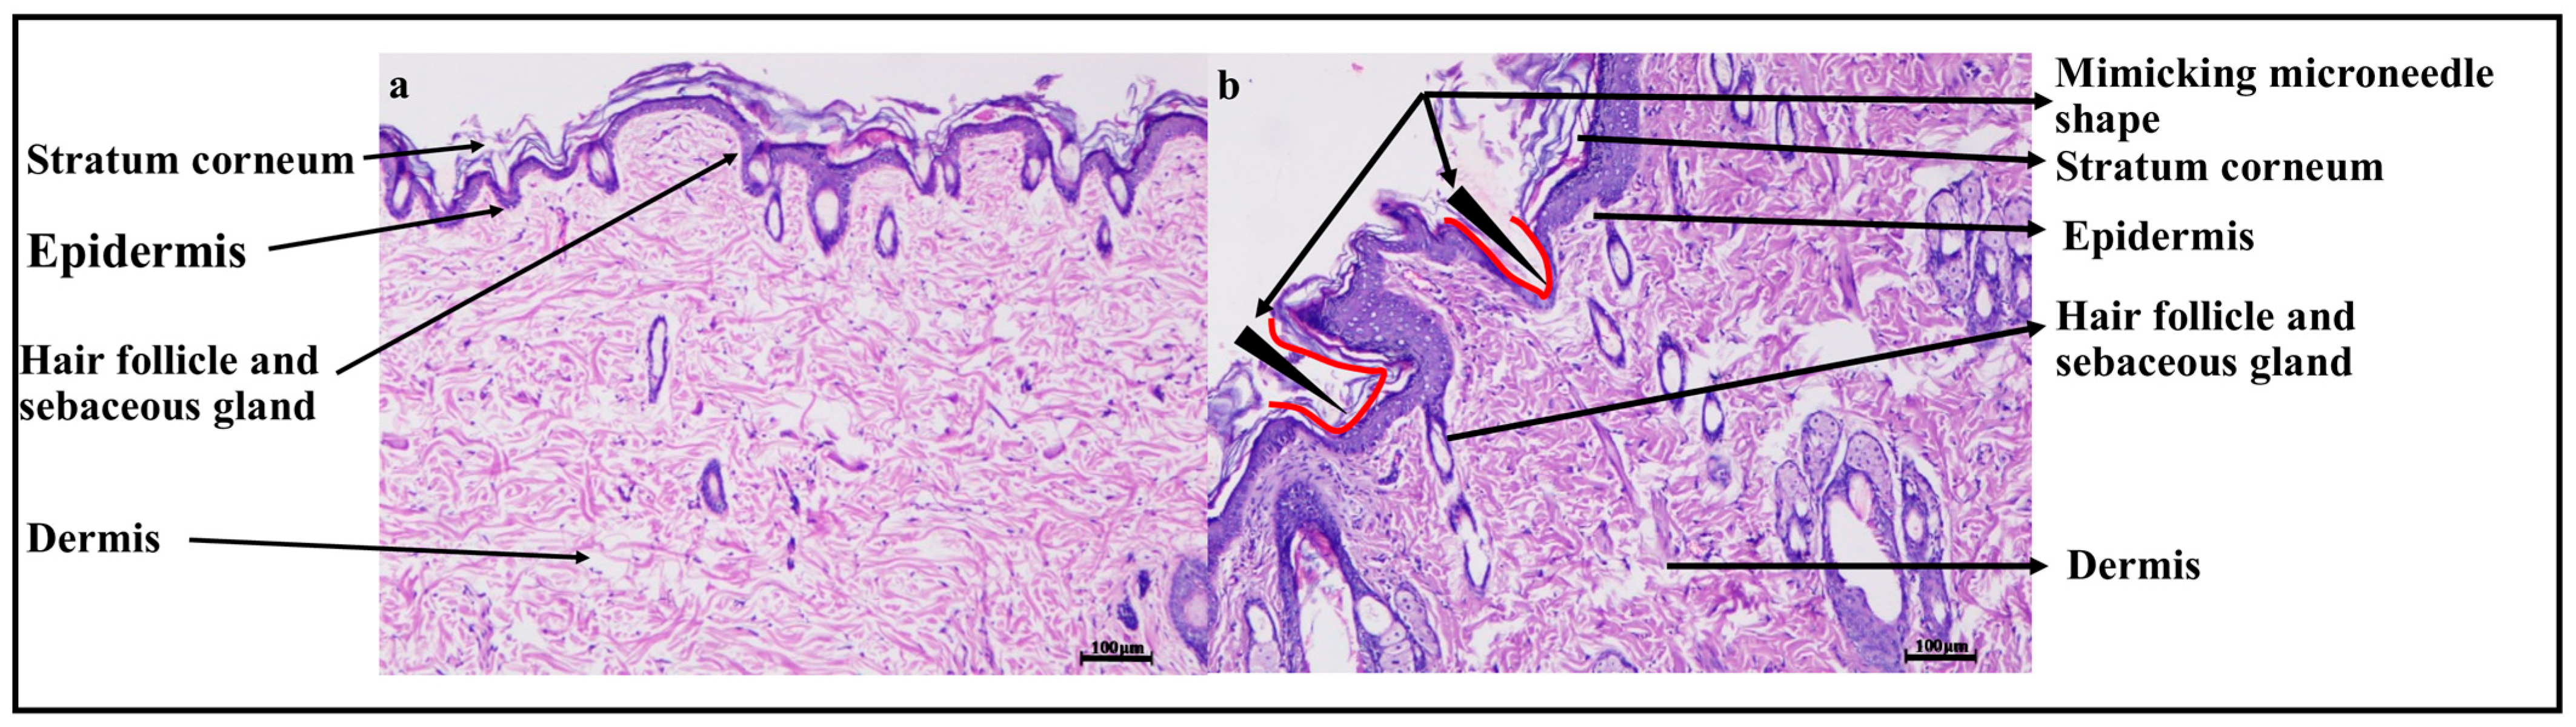

2.6.6. Histopathology Study

3.4.6. Histopathology Study